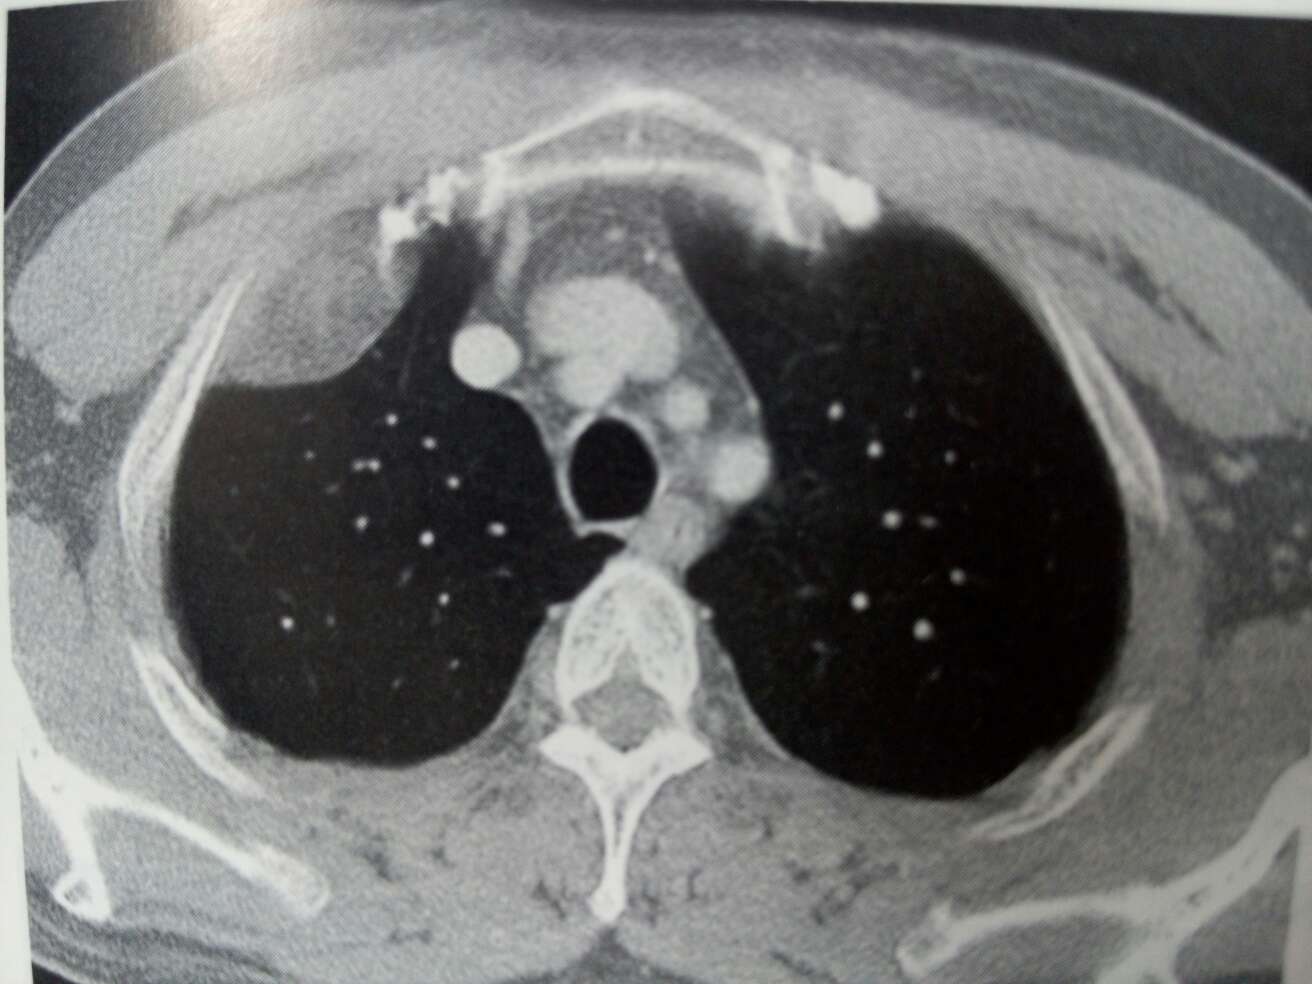

颈部肿物五年,肿胀不适一周入院。颈项部可见一肿物,6*7cm大小,质软,与周围组织稍粘连,不红,不热,未及搏动。是否行彩超检查